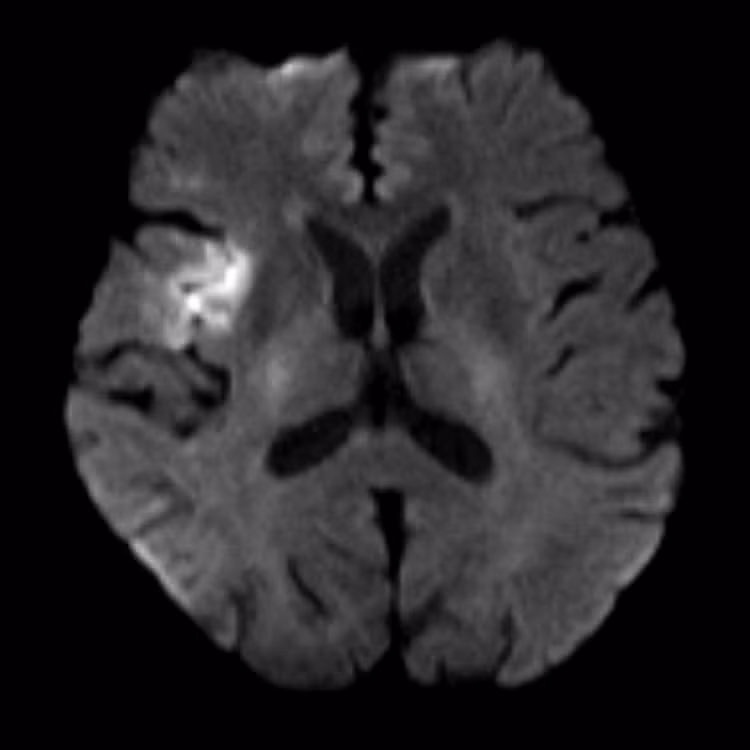

Hình MRI bệnh nhân T.L bị đột quỵ - Ảnh BVCC

“Báo động đỏ” được kích hoạt, cuộc chiến giành lại từng phút cho não bộ

Tại đây, ngay khi xác định được dấu hiệu đột quỵ, quy trình “báo động đỏ” lập tức được kích hoạt, quy tụ đội ngũ bác sĩ các chuyên khoa Cấp cứu, Nội thần kinh, Chẩn đoán hình ảnh. Trước đây, bệnh nhân có tiền sử tăng huyết áp và bệnh phổi tắc nghẽn mãn tính (COPD) nhưng không điều trị. Kết quả trên phim MRI cho thấy bệnh nhân bị đột quỵ nhồi máu não.